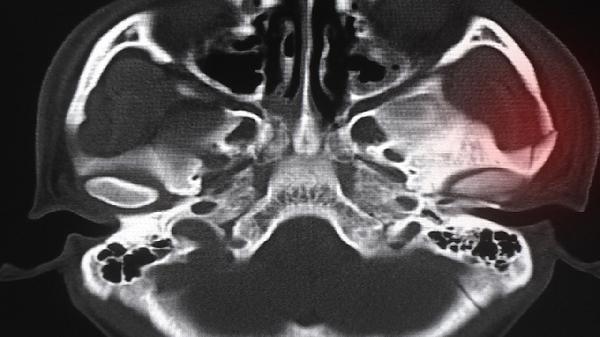

超过正常愈合时间后,骨折处仍存在反常运动或弹响感。西医检查可见骨折线清晰可见,中医辨证多属肝肾不足导致骨痂生成障碍,需配合续筋接骨类药物如骨碎补、自然铜,必要时考虑重新固定。

针对骨头不愈合问题,日常需保证钙质与胶原蛋白摄入,推荐饮用骨汤、食用黑芝麻等补肾壮骨食材。适度阳光照射促进维生素D合成,避免吸烟饮酒影响骨代谢。功能锻炼应在医师指导下循序渐进,可配合八段锦两手托天理三焦等柔和功法改善血液循环。若症状持续3个月以上或进行性加重,建议及时进行X线三维重建等检查,排除病理性因素如骨髓炎或骨肿瘤可能。中医调理期间可定期复查舌脉象,根据气血盛衰调整当归、黄芪等补益药物的配伍比例。